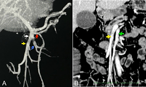

Constant maintenance of an alternative route of coronary flow in radical surgery for gastric cancer following coronary artery bypass grafting involving the right gastroepiploic artery: a case report

Naoki Ikari and others

Journal of Surgical Case Reports, Volume 2017, Issue 6, June 2017, rjx096, https://doi.org/10.1093/jscr/rjx096